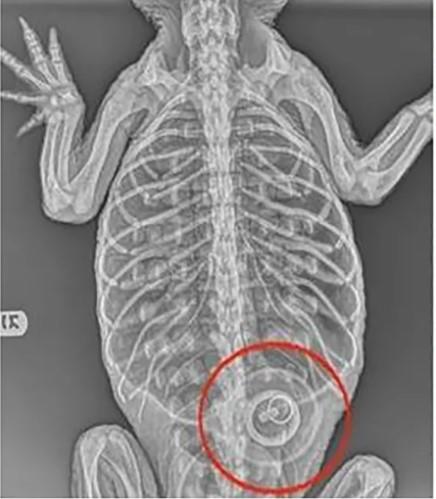

El zoológico dijo que las radiografías mostraron que el animal había ingerido un tapón de bañera de cuatro pulgadas que aún no se puede quitar.

“El caimán se encuentra actualmente en una condición demasiado debilitada para intentar quitarle el tapón”, dijo el Zoológico del Bronx en un comunicado. “Continuaremos brindándole atención de apoyo y determinaremos los próximos pasos en función de cómo responda al tratamiento”.